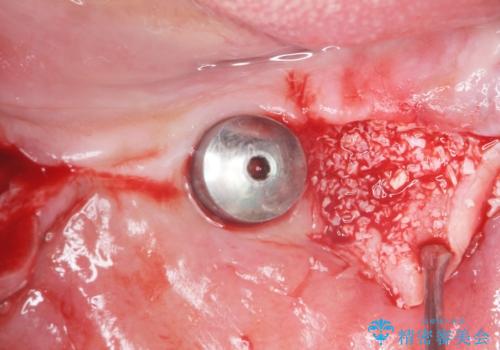

禁煙指導と歯周病治療後、左下臼歯部(左下467埋入)のインプラント治療を行いました。

インプラントの埋入は、抜歯後4ヶ月程度骨の治癒を待ったり、骨が少ない部分に関しては骨増生を行ったりして順次行いました。